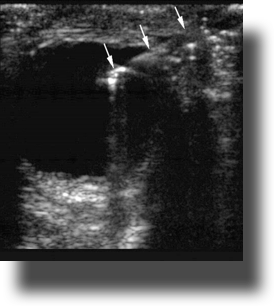

- Figure 6. Intraocular foreign body (Courtesy of Matthew Lyons, MD)

Ocular Foreign Body

- Intraocular foreign bodies are identified by their bright echogenic acoustic profile and either shadowing or reverberation artifacts seen in the usually echolucent vitreous.

- Ultrasound patterns of shadowing and comet tails may help differentiate foreign body materials.

- If there is concern that he foreign body has penetrated into the globe. Treat it as a globe rupture and contact ophthalmology immediately.

- In a porcine model, ocular ultrasound for detection of metal foreign bodies5:

- Sensitivity of 87.5%

- Specificity of 85.2%

- Negative predictive value: 85.2%